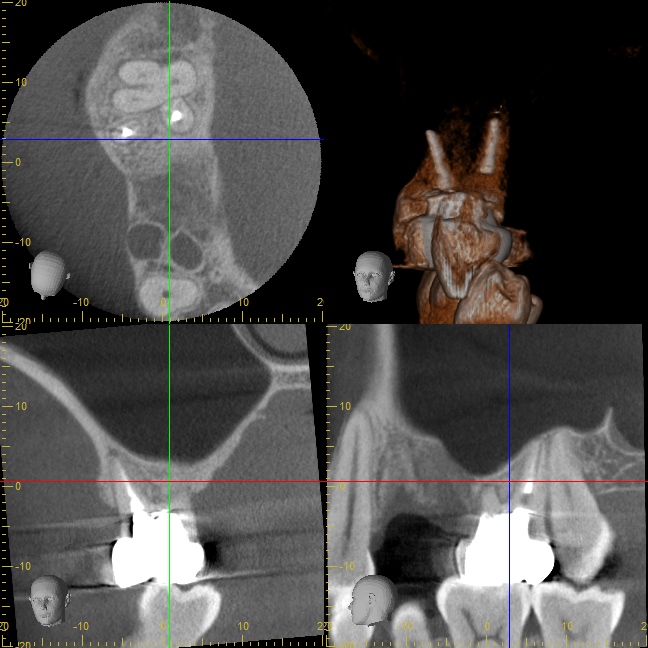

オペ後のCT写真

インプラント先端が少しだけ上顎洞(副鼻腔)に突き出てるように見えますが、問題はありません。

ご自分の骨で持ち上げられたスペースには血液がたまり、少しずつ骨に置換していきます。